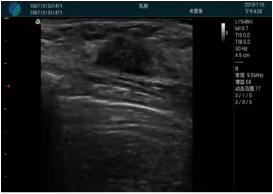

清晰顯示腺體內(nèi)低回聲快影,邊界清晰,包膜較光滑

確定進針路徑并實時監(jiān)測抽吸針與腫塊位置關系

抽吸針進入腫塊內(nèi)部進行旋切

抽吸過程中可見腫塊明顯縮小,并根據(jù)腫塊位置改變針道位置

抽吸旋切后再進行超聲復查,原腫塊區(qū)域未見殘留組織及出血